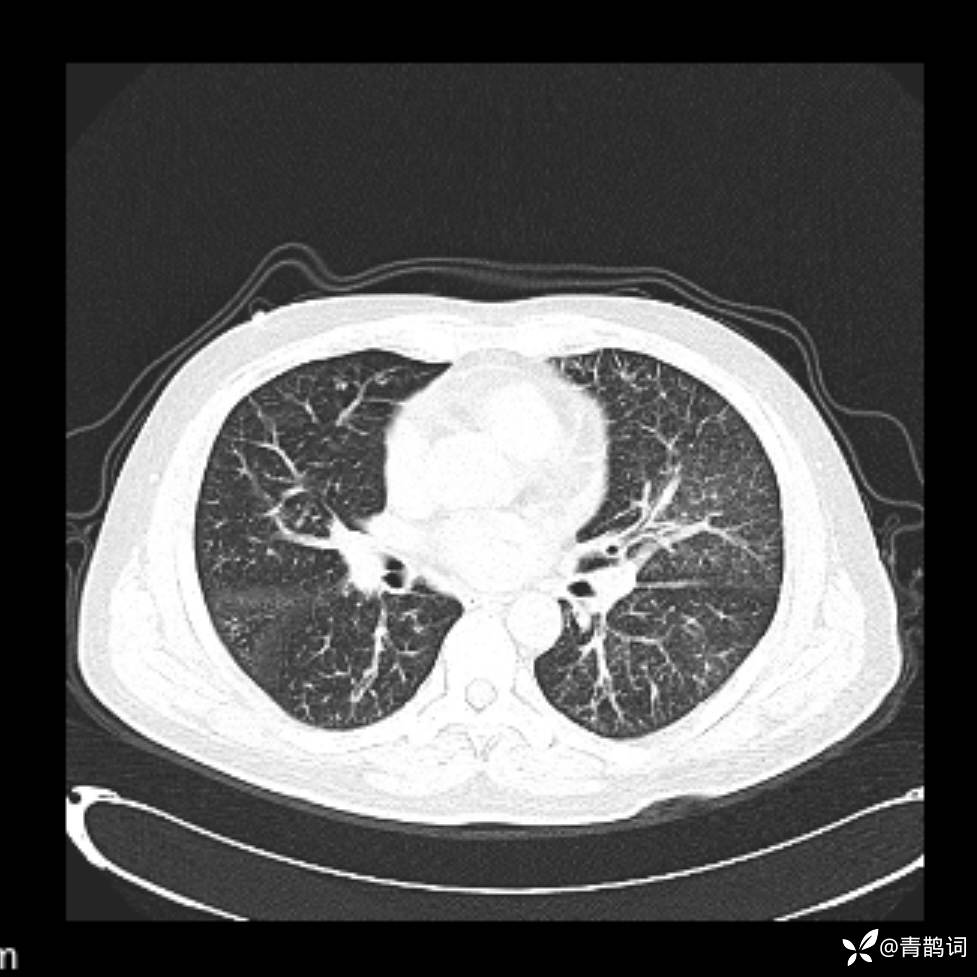

患者年龄:30岁。

患者性别:男。

简要病史:左颜面部肿胀2年,反复咳嗽咳痰,逐渐加重。

结合病史及影像学表现,期待评论区各位老师各抒己见~